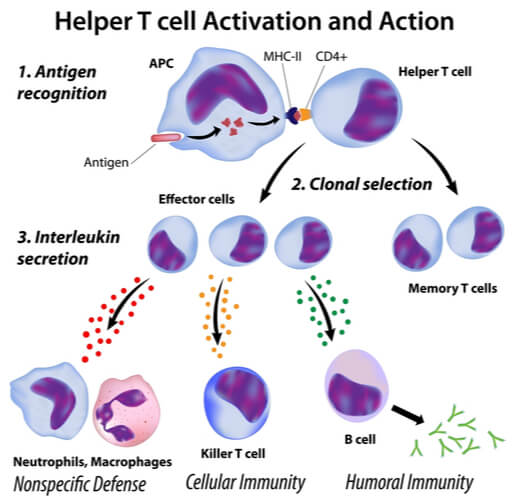

Sterilizing immunity can only occur through natural infection because the exposure process must take place in the mucus as it was intended by nature. After the infection is neutralized, a durable response includes resident memory T and B cells along with neutralizing IgA antibodies. These forces stand ready where they are most needed, and they are poised to take on future infections in their early stages.

Vaccine efficacy is promoted with absolutism, but a measurement of antibody levels in serum is only one small part of a much more intelligent system that includes mucus, mucous membranes, glands, the lymphatic system, cellular surveillance proteins, commensal microbes, T-cells, cytotoxic T-cells, and the T-Helper-1 and T-Helper-2 cells which work intracellularly to neutralize viruses like SARS-CoV-2. Vaccine makers trivialize the human immune system, giving off the impression that it is some programmable machine. The immune system is much more sophisticated than it is made out to be. The immune system contains many variables, and it differs from one person to the next.

Vaccine-induced antibodies are mostly useless because they circulate in the blood and away from the mucus – where they are actually needed. They also cannot work to the body’s benefit inside the cells, where virus replication actually occurs. As a general rule of thumb, antibodies are unable to bind with viruses that are replicating inside the cells. This is the job of the T-cells, which carry out the task of instructing infected cells to self-destruct.